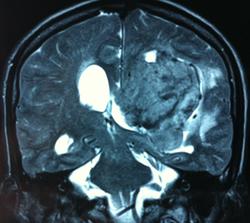

Начало вот здесь http://www.radiomed.ru/cases/kt-gms-obemnoe-obrazovanie-levoi-gemisfery-bolshogo-mozga-vnutrizheludochkovaya-meningioma. Пациент оперирован (меня сначала дезинформировали по поводу операции), перед операцией состояние ухудшилось, возникла правосторонняя гемиплегия, которая осталась и после декомпрессии. МРТ, КТ снимки и выписку предоставила супруга пациента, снимал на iphone, простите за качество, дисков с исследованиями не записывали. Надеюсь вопрос по данному случаю исчерпан.

Т2

И Вы считаете, что эта опухоль имеет интравентрикулярную локализацию?

Изначально по КТ я так предпологал, а теперь на 100% уверен, разве МРТ это не показало? Гистологически - менингиома, опухоль мозговой оболочки. Покажите, пожалуйста, образование где-нибудь прилежит к костям, где есть мозговая оболочка? Я не вижу, зато отчетливо вижу в левом боковом желудочке из оболочек сосудистого сплетения. Что вас еще смущает? По-моему, предостаточно фактов, чтобы развеять все сомнения.

Мне видится так. Иначе в данной локализации просто неоткуда расти оболочечной опухоли. На контрольной КТ, после декомпрессии, когда срединные структуры стали действительно срединны, правое обызвествленное сосудистое сплетение видно отчетливо, а левое, где оно? Ведь если бы образование компремировало, то после операции, когда часть мозга пролабировало в трепанационное отверстие мы бы увидели и левое сосудистое сплетение, но оно интимно связано с образованием и даже "потянулось" за ним в сторону декомпрессионного отверстия, потому что это и есть "росток" откуда выросла опухоль.

У меня вопрос (извините, если тупой - я-не волшебник, я только учусь=) - мне кажется, что в центре образования есть участки пустоты потока (сосуды), а разве менингиома склонна к такому неоангиогенезу? просто прочитала все вышенаписанное, вроде полностью согласна, но как вариант закралась мысль о сосудистой опухоли из сплетения бок.желудков. Если я совсем не права, прошу пояснить. Хочется все понимать уже на первых годах работы.) Заранее благодарю.